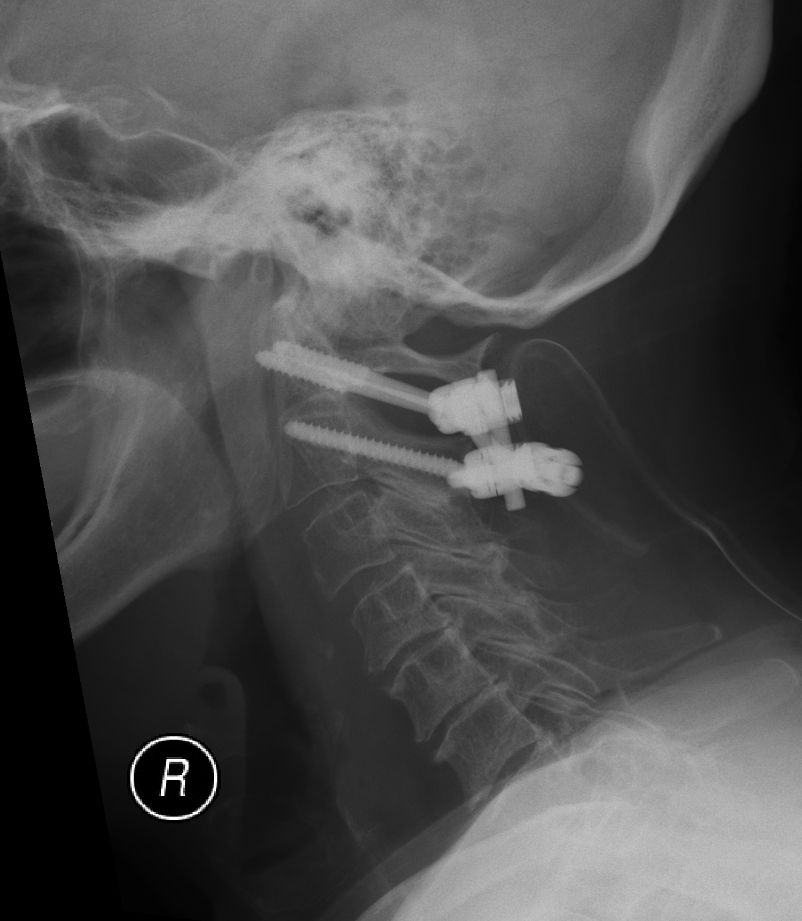

• Zlomenina dens axis (obratel C2), která je typická ve starším věku. Ošetření pomocí zadní stabilizace.